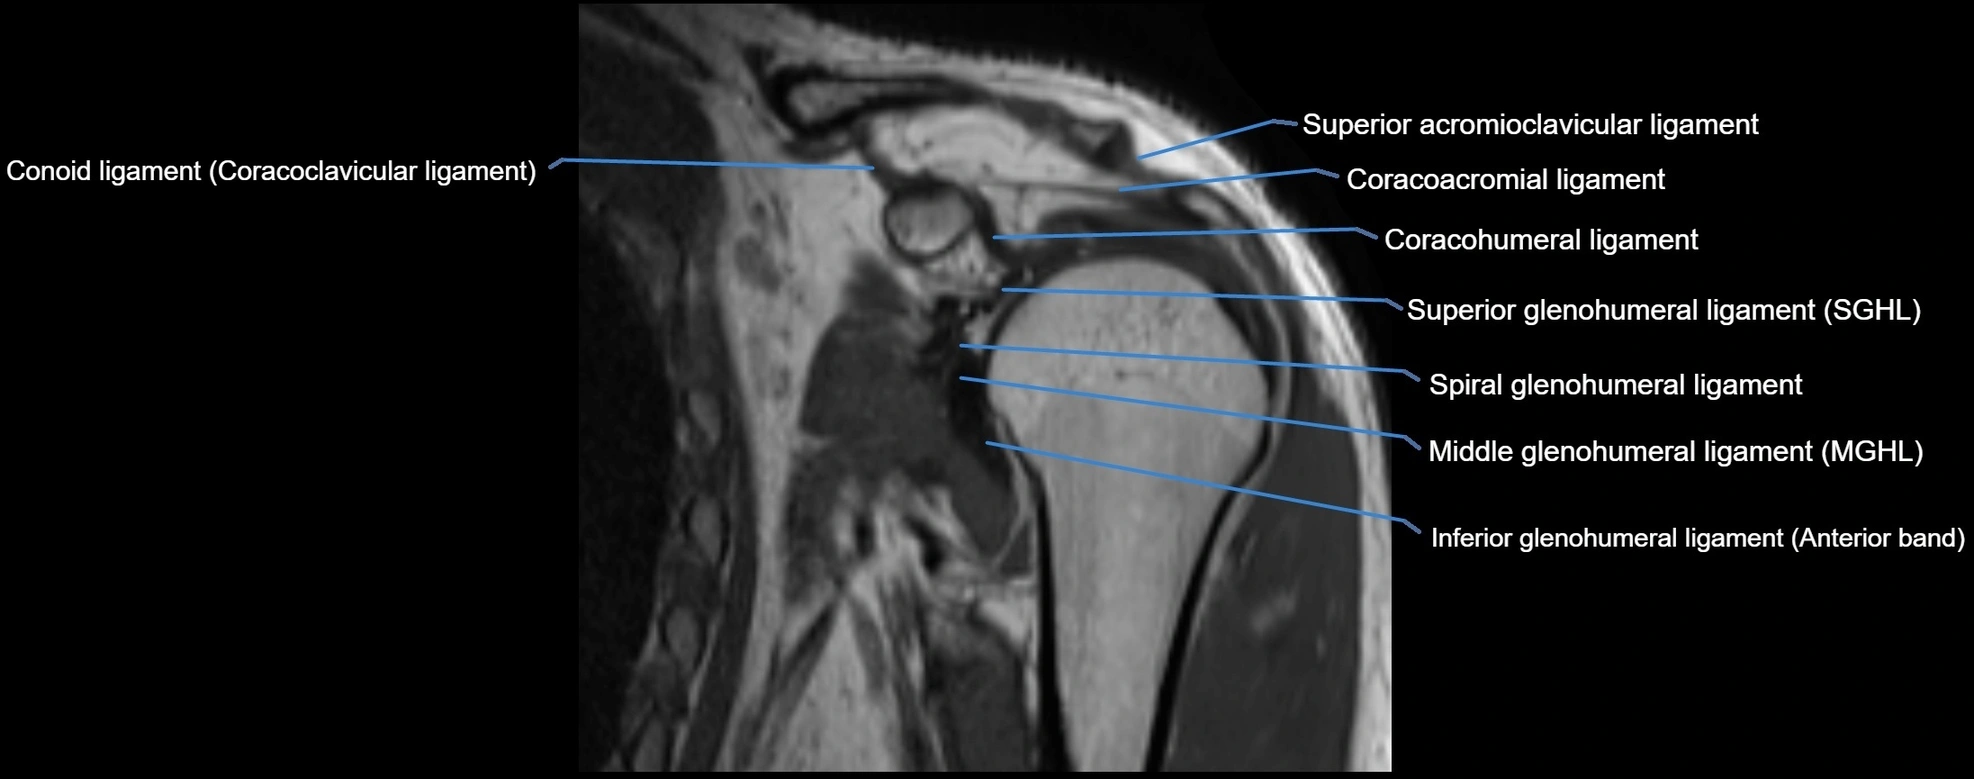

CT image

image